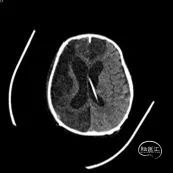

术后1月